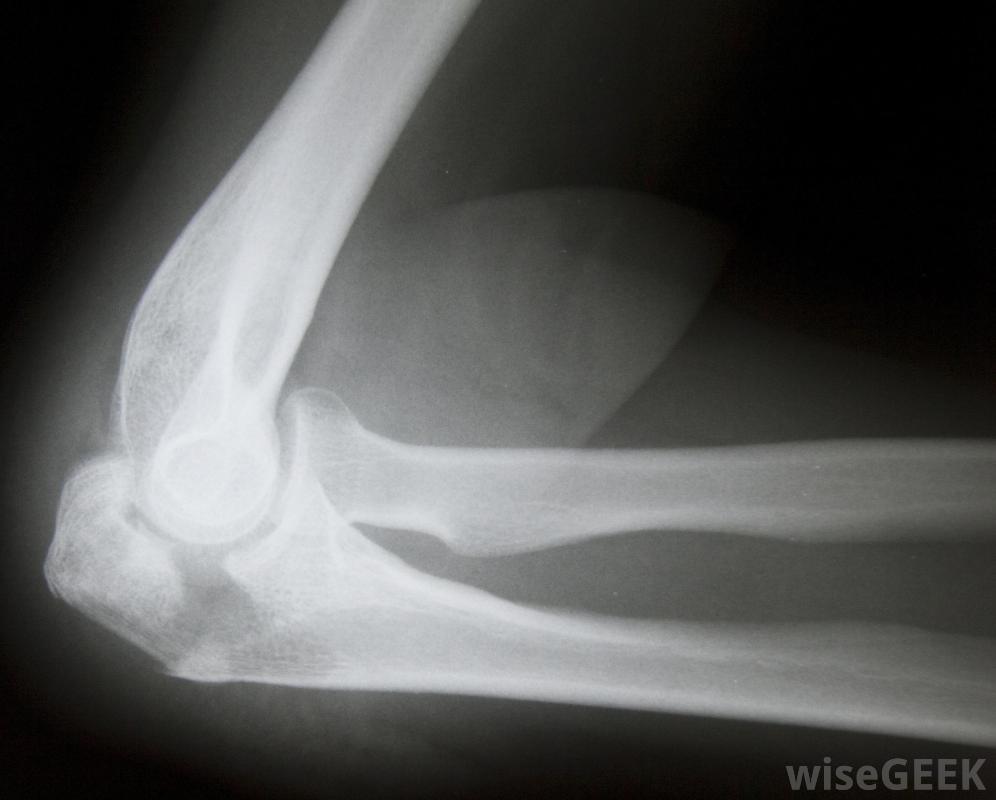

什么是鷹嘴骨折(Olecranon Fracture)?

尺骨鷹嘴骨折是指肘關節底部的骨折。尺骨從手腕一直延伸到肘部后部,在那里有一個叫做尺骨鷹嘴的部分形成了我們熟悉的骨性突出物。尺骨鷹嘴骨折通常發生在摔倒或直接擊中肘部的情況下,導致劇烈的、立即的疼痛和腫脹大多數骨折都是保守治療,將手臂放在吊帶或軟石膏上,等待骨頭自行愈合。嚴重的鷹嘴骨折和關節脫位需要手術來糾正組織損傷。X光有助于確定尺骨鷹嘴骨折的確切位置和嚴重程度。尺骨鷹嘴本身是一塊堅固的骨頭,但由于它靠近身體,它仍然很容易骨折骨骼沒有被周圍組織很好的保護,在活躍的人群中是一個非常常見的創傷部位。尺骨骨折可能是由于鈍器的直接撞擊、大部分沖擊力被肘部吸收的墜落、或是關節脫臼的笨拙彎曲或扭轉運動造成的老年人也有患尺骨鷹嘴骨折的風險,因為他們的骨頭通常比較脆弱,而且更容易摔倒尺骨鷹嘴骨折會立即引起肘部疼痛尺骨鷹嘴骨折通常會導致突然疼痛,很快就會伴有頭暈和惡心。肘關節腫脹,手臂無法移動。在肘部受傷的情況下,用吊索固定關節非常重要,直到可以尋求專業醫療護理應立即送至急診室接受正確診斷和止痛藥物。參加接觸性運動(如摔跤)的人可能發生尺骨鷹嘴骨折進入急診室后,醫生通常會口服或注射藥物來緩解疼痛和腫脹的癥狀。醫生可以對肘部進行x光和磁共振成像掃描,以確定確切的情況骨折的位置和嚴重程度。大多數尺骨鷹嘴骨折不會對骨骼或周圍結構造成嚴重損害。患者只需戴上吊索或支架數周,并定期接受醫生檢查,以確保骨骼正確愈合。吊帶可在兩個月內取下,此時患者可能需要進行鍛煉或參加物理治療以恢復體力。尺骨鷹嘴骨折可能會導致疼痛和惡心如果尺骨粉碎成小塊或從肘關節脫臼,則認為尺骨骨折很嚴重。嚴重骨折通常需要手術。熟練的外科醫生可以在肘部切開,去除骨碎片,縫合受損組織,并將鷹嘴重新定位。有些骨折需要放置螺釘或人造材料來幫助固定骨骼。物理治療對于幫助患者在手術后增強力量和柔韌性非常重要src="/img/0801/x-ray-of-broken-elbow.jpg"/>鷹嘴骨折最常在急診科接受治療。治療尺骨鷹嘴骨折可能需要臂吊帶肘關節。尺骨鷹嘴骨折是尺骨的一種骨折,它延伸到關節周圍。